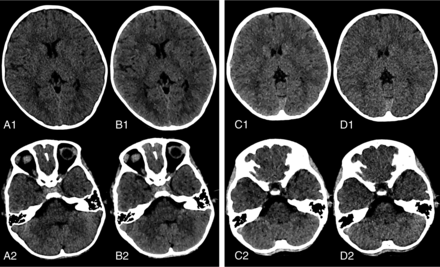

Conventional images. Placement of ROIs in cortical GM and the thalamic parenchyma (ROIs in the black circle), in juxtacortical WM and the posterior limb of the internal capsule (ROIs in red circles), as well as close to the calvaria and in the medulla oblongata (ROIs in green circles) on the axial plane, showing the basal ganglia (A) and the posterior fossa (B).

Representative images showing improved image quality in the supratentorial and infratentorial brain parenchyma for conventional images and 60-keV VMIs acquired using 250 and 180 mAs. Axial reconstruction conventional image (A) and 60-keV VMI (B) for nonenhanced brain CT scans acquired with 250 mAs in a 6-year-old girl with neuroblastoma in the retroperitoneal area. Axial reconstruction conventional image (D) and 60-keV VMI (C) for a nonenhanced brain CT scan acquired with 180 mAs in a 6-year-old girl with exotropia in the eye. GWMA (B1, C1), SSA, and PFAA (B2, C2) and overall image quality were better for 60-keV VMIs compared with conventional images (A1, D1, A2, and D2), respectively. Subjective image-quality indices were similar in 60-keV VMIs between the 250-mAs (B1, B2) and 180-mAs (C1, C2) groups. Window settings were kept identical for better comparability (level, 35; width, 70).